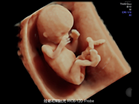

4D 超音波診断エコー

当クリニックで導入している最新式の3D/4Dエコー検査機は お腹の中の赤ちゃんの背伸びをしたりあくびをしたり指しゃぶりをしたり等の様子をリアルタイムに立体画像で見ることが可能です。

映像はSDカードに記録していきます。

お子様の胎内での成長過程を このすばらしい画像で記念に残してあげて下さい。

尚、赤ちゃんの姿勢や向きによってお顔などが十分に見られない時もありますのでご了承下さい。

- 最新機種で最上位機種の産婦人科向け超音波画像診断装置「Voluson E10」を導入致しております。

リアリティのある透明感と立体感を実現して、命の躍動をクリアに描き出します。